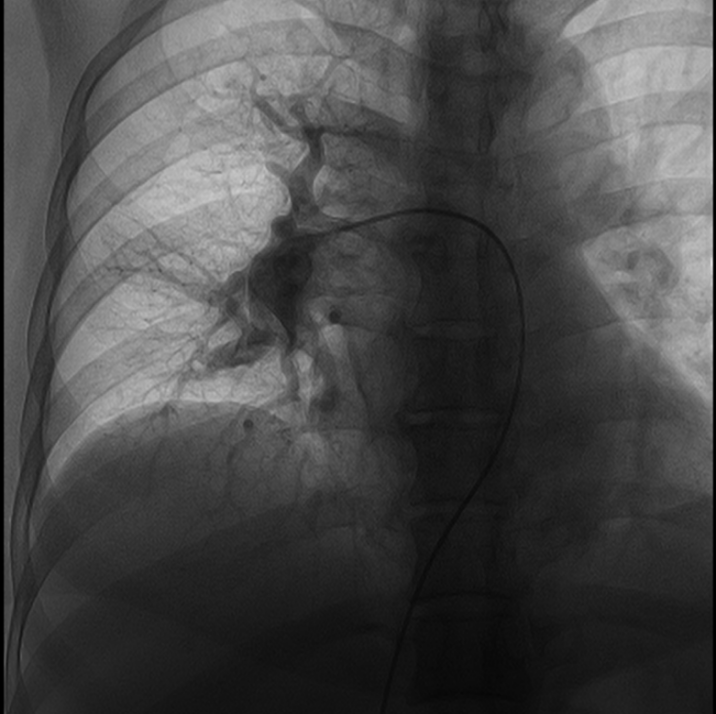

患者慕名至我院后,我科专家进一步对其进行了相关检查,最终诊断为:慢性血栓栓塞性肺动脉高压。心内科周亚峰副院长、陈弹主任、赵良平主任及团队成员进行深入讨论,并邀请呼吸科、血管外科与介入科等进行多学科(MDT)会诊,最终决定对其进行右心导管及肺动脉造影检查,结果提示肺动脉收缩压52mmHg,平均肺动脉压33mmHg,左右各肺动脉及其分支多发栓塞,可见多处血栓影及马赛克征。对右肺动脉A3、左肺动脉A1+2、左肺动脉A9行球囊扩张术,扩张后复查造影远端血流恢复良好。手术后患者的症状得到明显改善,心功能逐渐恢复,住院5天后平稳出院。出院后患者继续进行家庭氧疗、抗凝、利奥西呱降肺动脉压力等治疗,并密切随访中。随访至今,患者情况良好。

行球囊扩张后